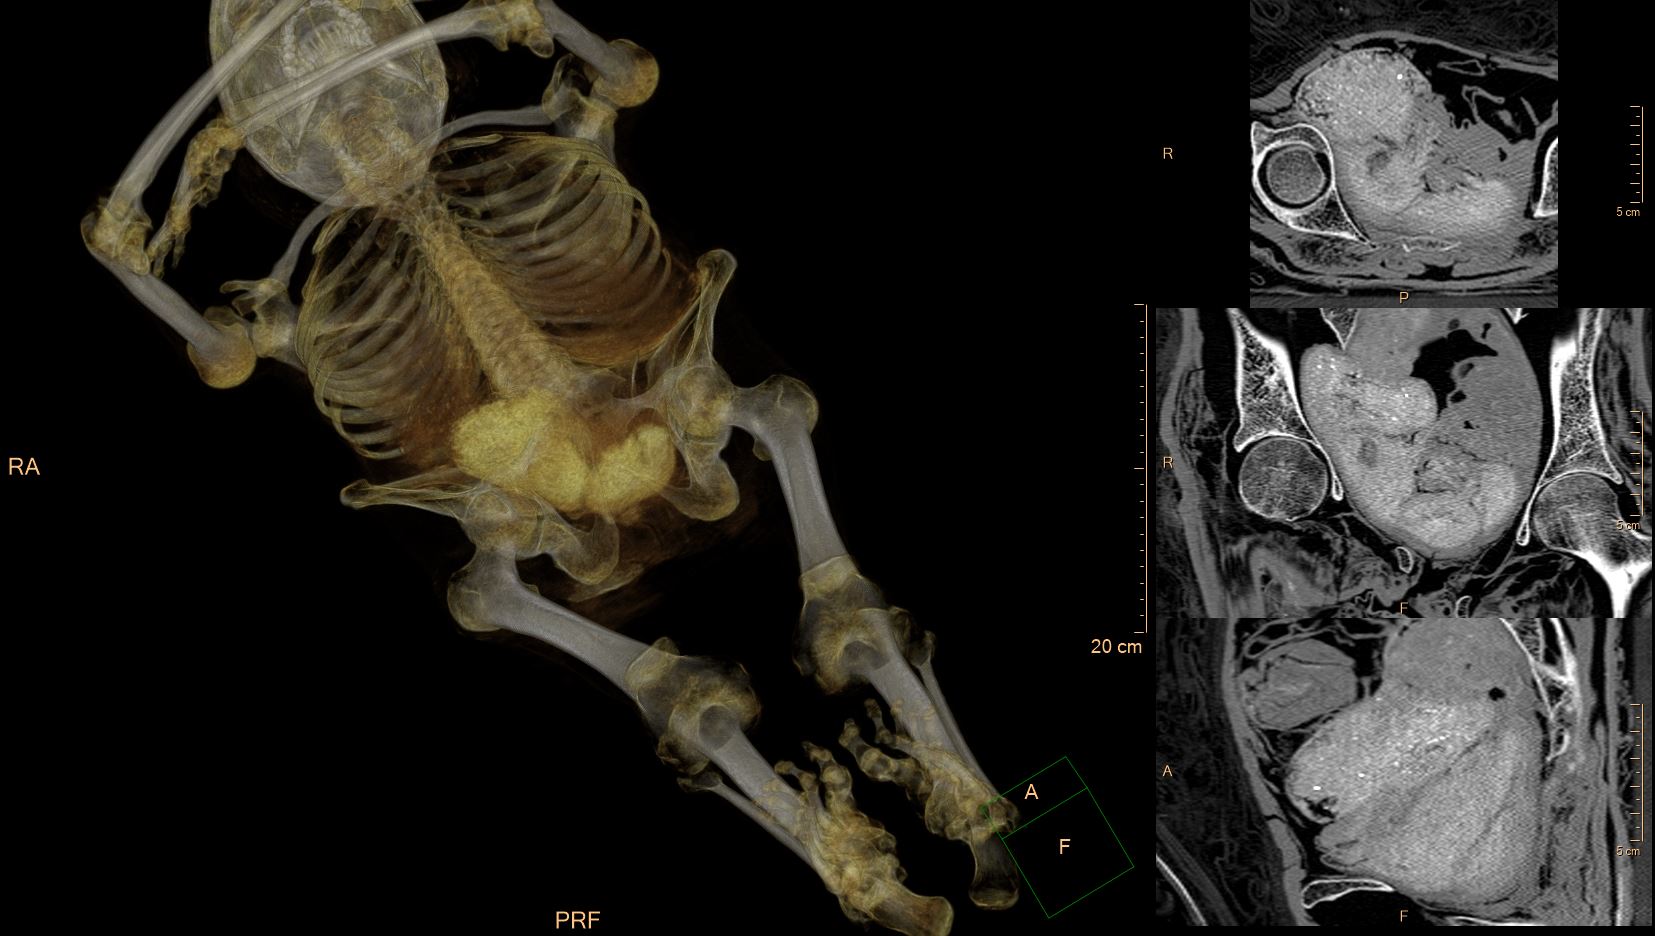

The initial illustration comes from the paper of K. Braulińska et al.: Innovative approach to the verification of the alleged pregnancy and cancer in the Warsaw mummy: international case study with extended research, in the journal Archaeological and Anthropological Sciences, 17:65, 2025, Fig. 11 (fragment). It represents the 2D and 3D reconstructions of the mummy’s skull imaged using computed tomography. CT scan and postprocessing: Ł. Kownacki